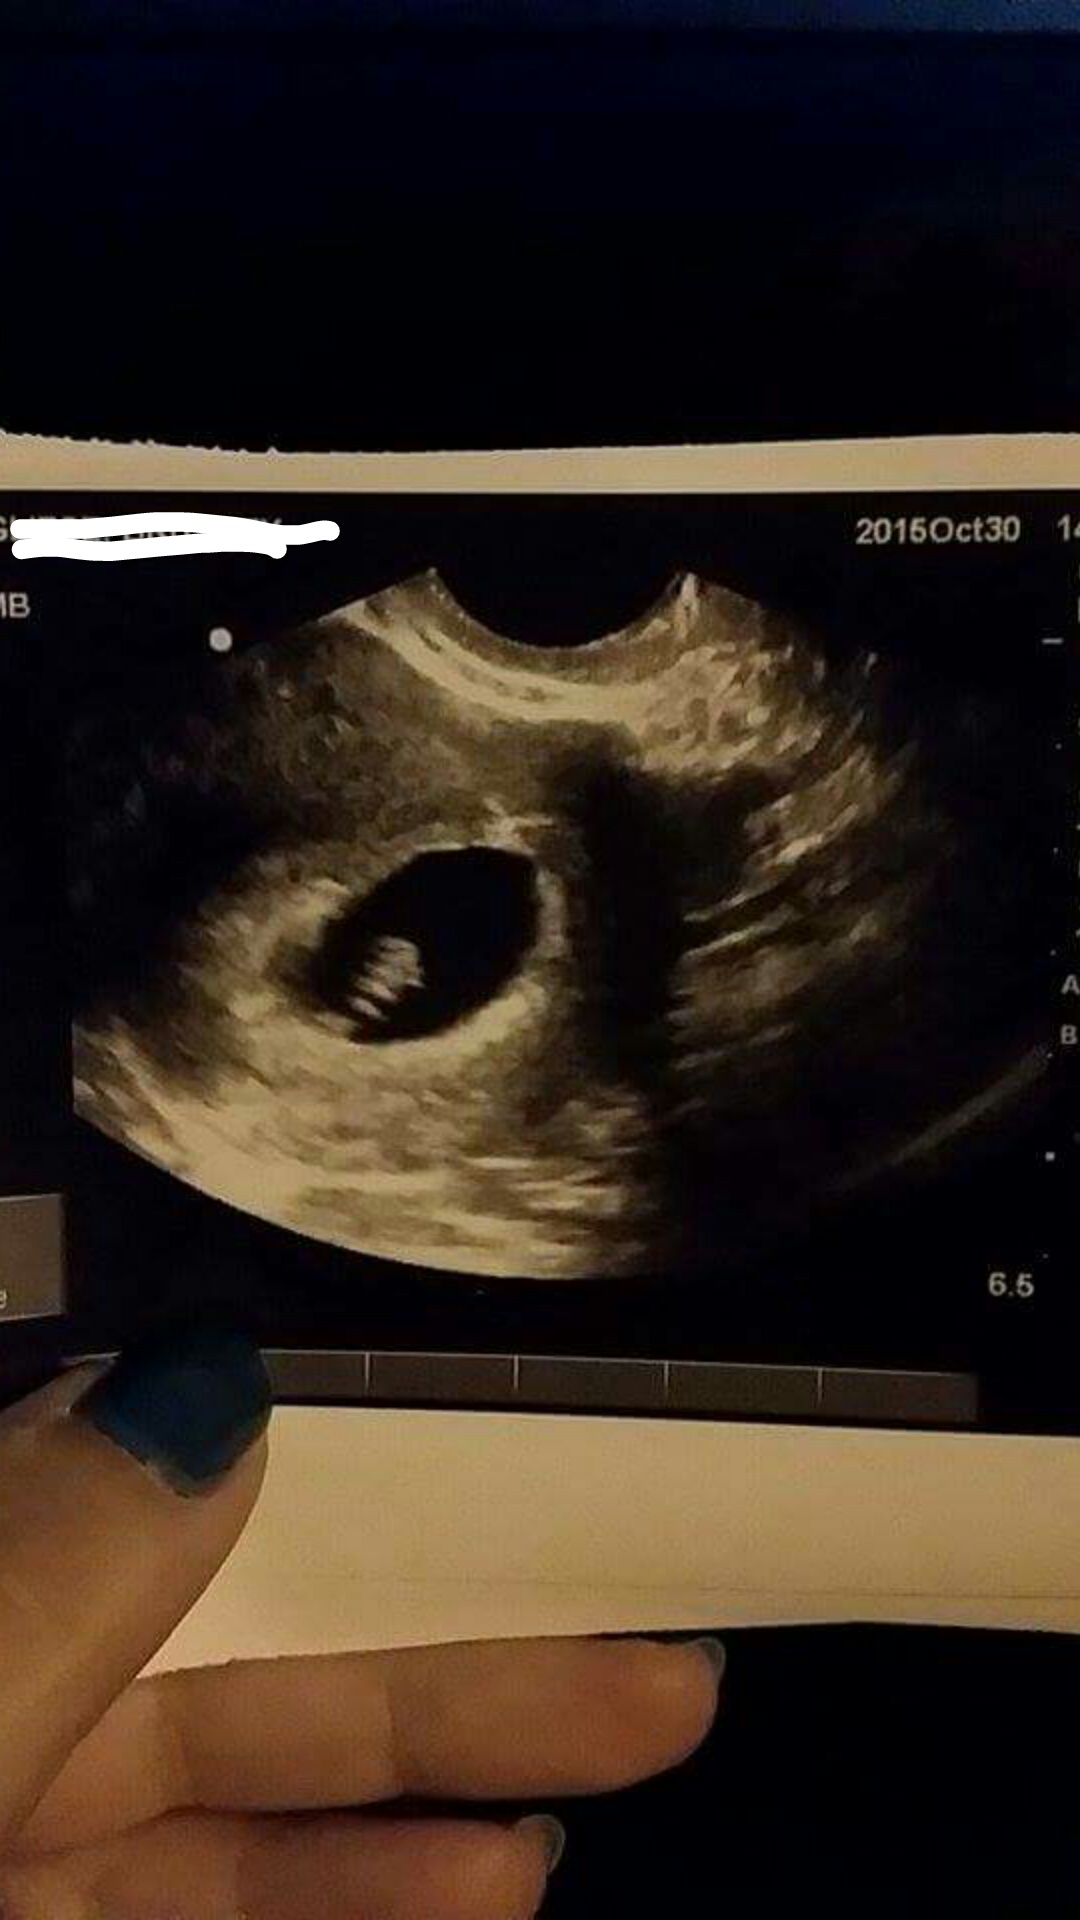

According to my lmp I should be 9w3d today. Last Tuesday I would up in the er for dehydration and bleeding and they did an ultrasound. I should have been 7w6d and baby was measuring 6w1d. Baby had a heartbeat of 108.

Attached u/s first from 10/20 then from 10/30